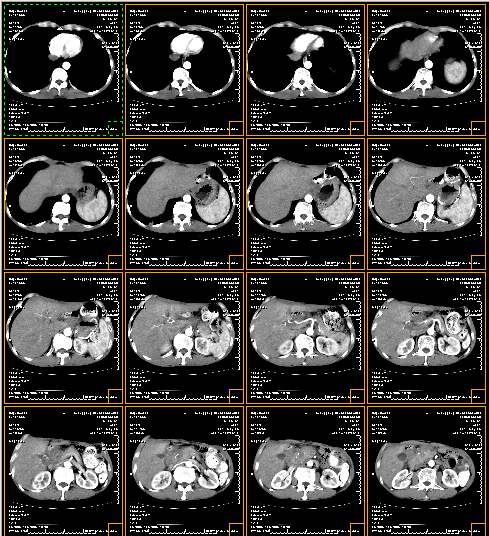

本模型用于肺癌篩查CT檢查,螺旋CT,多排螺旋CT的操作

參考圖,以實際供貨為準。